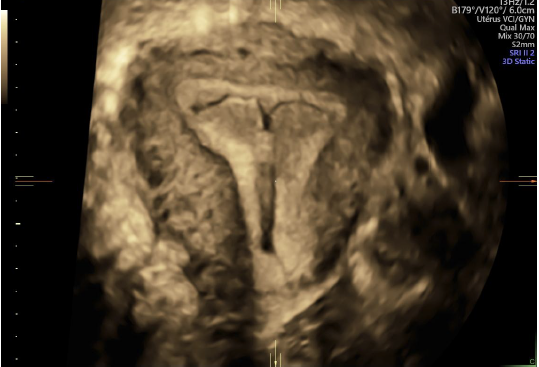

• la prescription de la contraception (pilule, pose implant et dispositif Intra Utérin),

• les échographies gynécologiques,